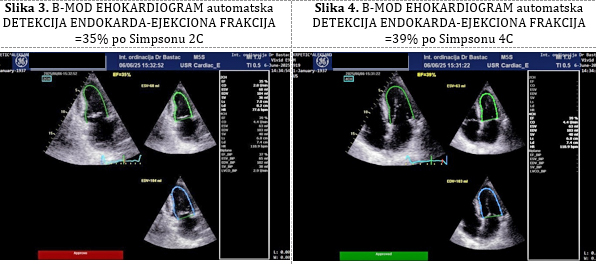

EHOKARDIOGRAFIJA: U nalazu dominira dilatacija leve

komore, normalne debljine zidova leve komore , bez hipertrofije

miokarda i sa sniženom globalnom sistolnom funkcijom: ejekciona

frakcija (EF) leve komore je 39% u M modu (Teicholtz) (Slika 2), a

po Simpsonu 35% i 39%, a biplejn 37% (Slika 3,4).

Slika 3. B-MOD EHOKARDIOGRAM automatska DETEKCIJA

ENDOKARDA-EJEKCIONA FRAKCIJA =35% po Simpsonu 2C Slika 4. B-MOD

EHOKARDIOGRAM automatska DETEKCIJA ENDOKARDA-EJEKCIONA FRAKCIJA =39%

po Simpsonu 4C